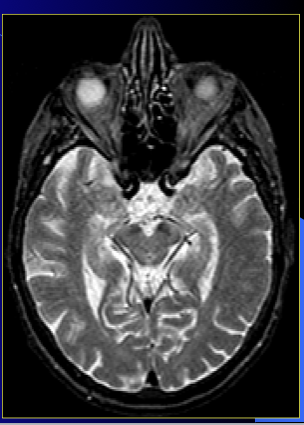

is this T1 or T2?

T2